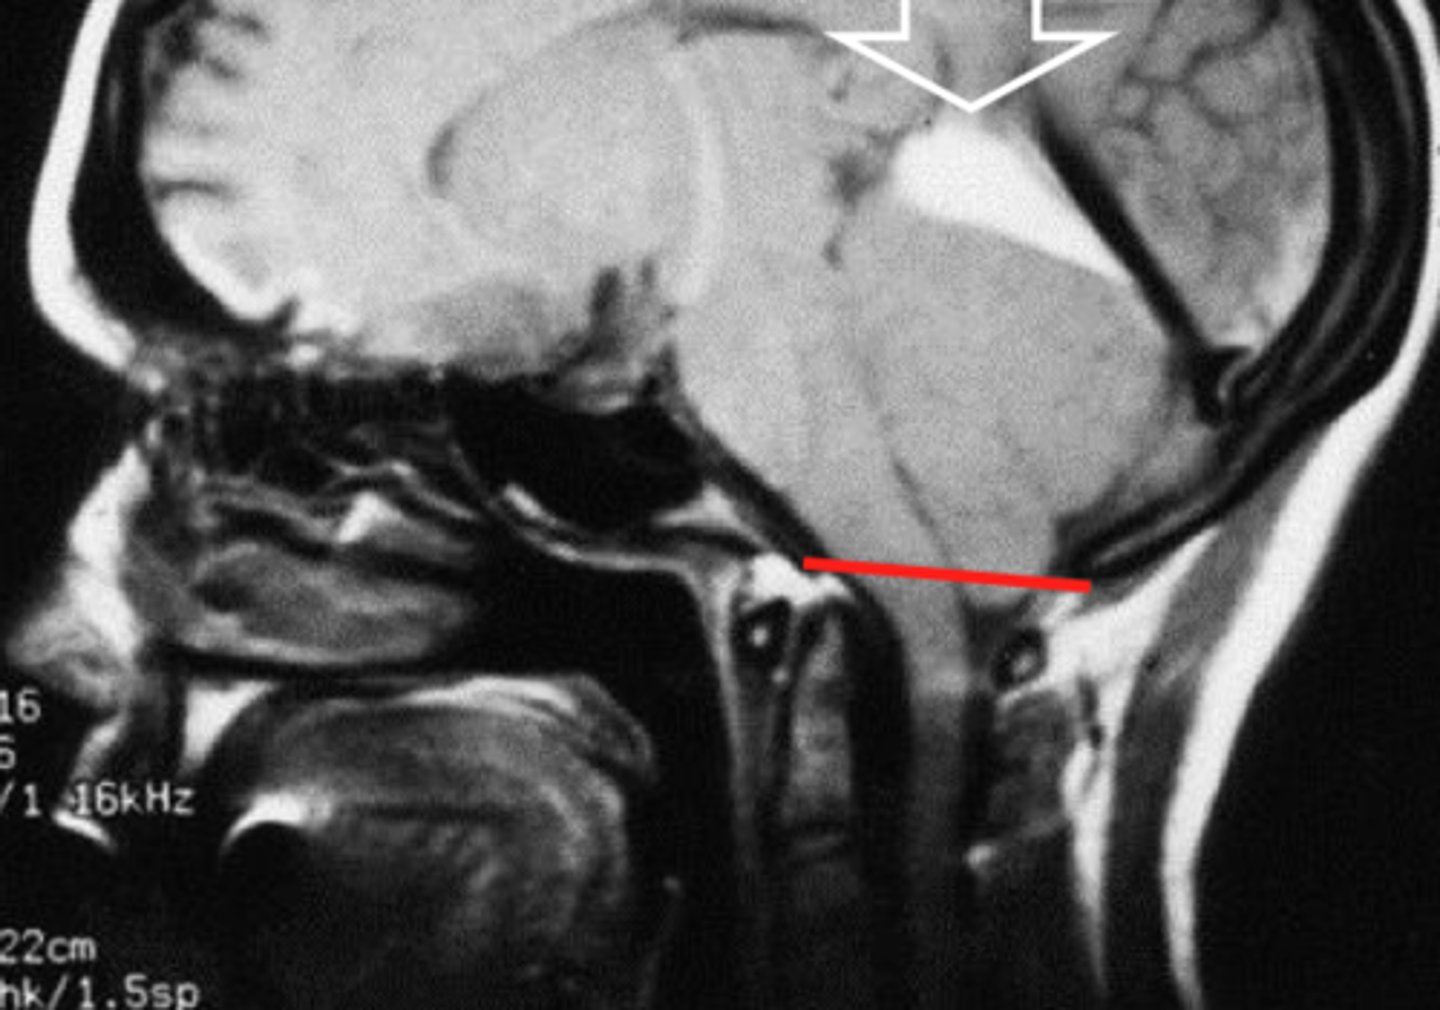

cervicomedullary junction

transition between the medulla oblongata and upper cervical spinal cord (C1-C2) that is located at the level of the foramen magnum

*houses ascending/descending tracts (decussation) and nuclei that influence breathing, CV control, and CN 9-12

*orange line on picture

tentorium cerbelli

horizontal meningeal fold of the dura mater that separates the cerebellum from the occipital lobe

*contains passage for brainstem (tentorial notch)

transtentorial (uncal) herniation

herniation of the brain where the temporal lobe shifts through the tentorial notch

*1 on diagram

tonsillar herniation

herniation of the brain where cerebellar tonsils descend through the foramen magnum